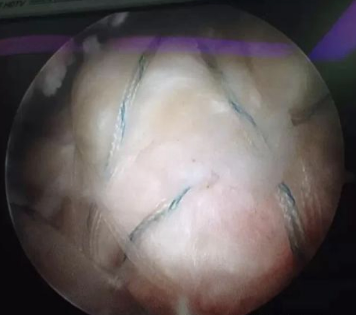

3.植入錨釘

1. 植入內(nèi)外側(cè)錨釘縫合肩袖,根據(jù)撕裂的大小和類型,初步確定錨釘位置。在肩袖肌腱原來(lái)的止點(diǎn)鉆孔,而后植入帶有縫線的內(nèi)排錨釘。

2. 在其外側(cè)植入外排錨釘,縫合線呈“橋式”下壓肌腱在肱骨頭上,使得肌腱和骨的貼合更緊密,有利于后續(xù)的腱骨愈合。

肩袖縫合示意